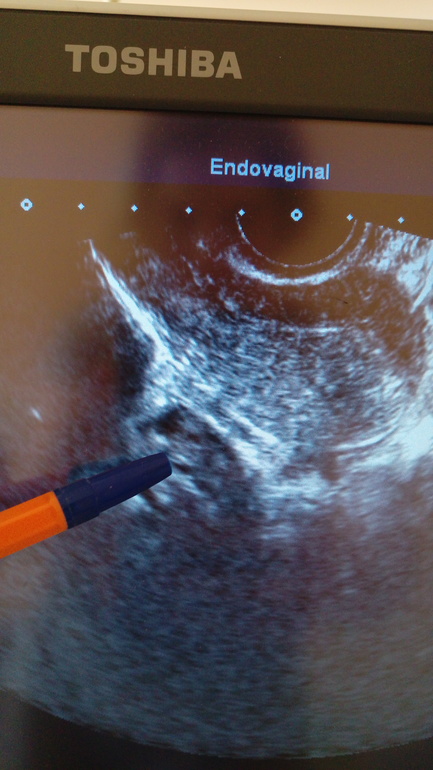

Может,но месячных так и нет была на УЗИ ВОТ СНИМОК 25 МАЯ